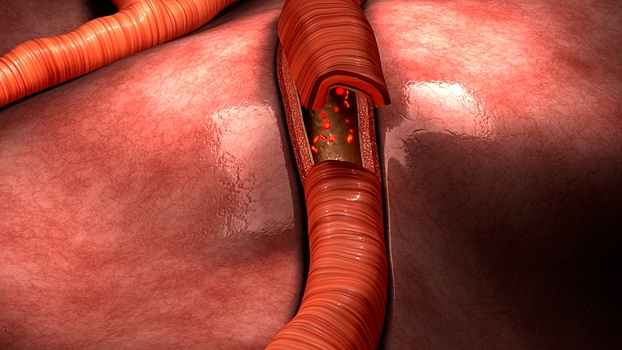

Стало известно, какие четыре фактора ученые называют разрушительными для сосудов. Об этом пишет Focus со ссылкой на медицинского директора Центра профилактики и спортивной медицины Мюнхенского технического университета Мартин Халле. Он считает, что это сахар, холестерин, курение и высокое кровяное давление.

Врач отметил, что никотин приводит к сужению сосудов, это препятствует кровоснабжению отдельных участков организма.

Повышенный уровень сахара в крови врач считает одним из факторов, плохо влияющих на сосуды. По его мнению, это приводит к повреждению внутренней стенки сосудов аналогично воздействию никотина.

А холестерин откладывается под сосудистыми клетками и с течением лет затвердевает в артериях.

Из-за высокого кровяного давления, считает медик, сосуды могут попросту лопнуть.